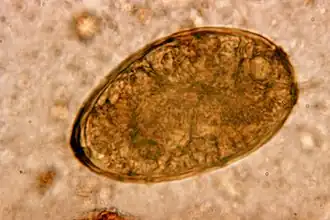

| Eitje van Paragonimus westermani | ||||||||||||||

De ziekte paragonimiasis wordt veroorzaakt door het eten van zoetwaterkreeften en andere kreeftachtigen die niet voldoende zijn doorgekookt. Hierin bevinden zich ingekapselde larven (metacercaria). Deze larven doorlopen een volgend stadium en dringen via het maag-darmstelsel de buikholte in en boren zich door het middenrif en komen zo terecht in de longen waar ze eieren leggen en ze zich inkapselen. De eitjes zijn 0,080 tot 0,120 mm lang en 0,045 tot 0,070 mm breed en bruingeel van kleur. Deze eitjes worden opgehoest en kunnen direct, of via ontlasting in het water terechtkomen. Daar komen de eitjes uit en veranderen in een vrijlevende larve (het miracidium stadium) die zich met trilhaartjes voortbeweegt. Deze larven zoeken een slak op. Er zijn 54 soorten slakken bekend uit de klasse Neotaenioglossa die als tussengastheer kunnen optreden. De larven verlaten de slakken en verplaatsen zich opnieuw in een vrij levend stadium (cercaria-stadium) en nestelen zich in een kreeftachtige.